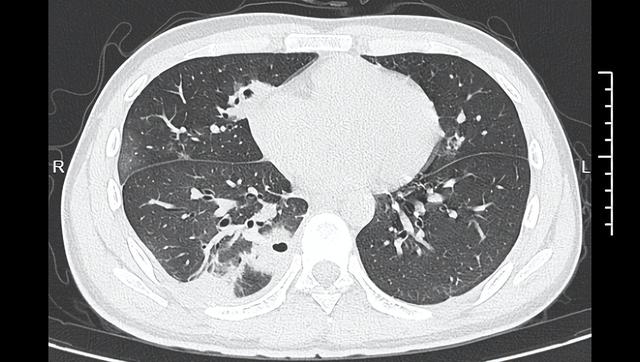

至第3天,小林燒到攝氏39度,趕緊到寧波大學附設第一醫院就診,應診的丁群力主任醫師一看其症狀,立刻安排CT檢查,結果顯示小林的肺部有10多個空洞,部分肺組織已壞死,是典型的血源性肺膿瘍。

進一步細菌培養和基因檢測顯示,小林的血液檢出金黃色葡萄球菌,這種細菌藏在每個人的皮膚表面,丁群力解釋 「『罪魁禍首』就是那顆被擠掉的痘痘,這顆痘痘長在臉部『危險三角區』,擠痘痘時的壓力把細菌推進了血管,引發了敗血症,接著細菌順著血流跑到肺部,侵蝕肺組織」。

另一方面,擠壓的壓力容易把這些細菌強行推進血管裡,沒有靜脈瓣的阻擋,細菌可順著血液自由擴散,往上進入顱內,引發腦膜炎、腦膿瘍等疾病,往下順著全身血液循環,跑到肺部、肝臟等器官,引發嚴重感染。像小林這樣,當細菌跑到肺組織,會破壞肺細胞,引發局部發炎,隨著發炎加重,肺組織會逐漸壞死、液化,最後形成一個空洞。